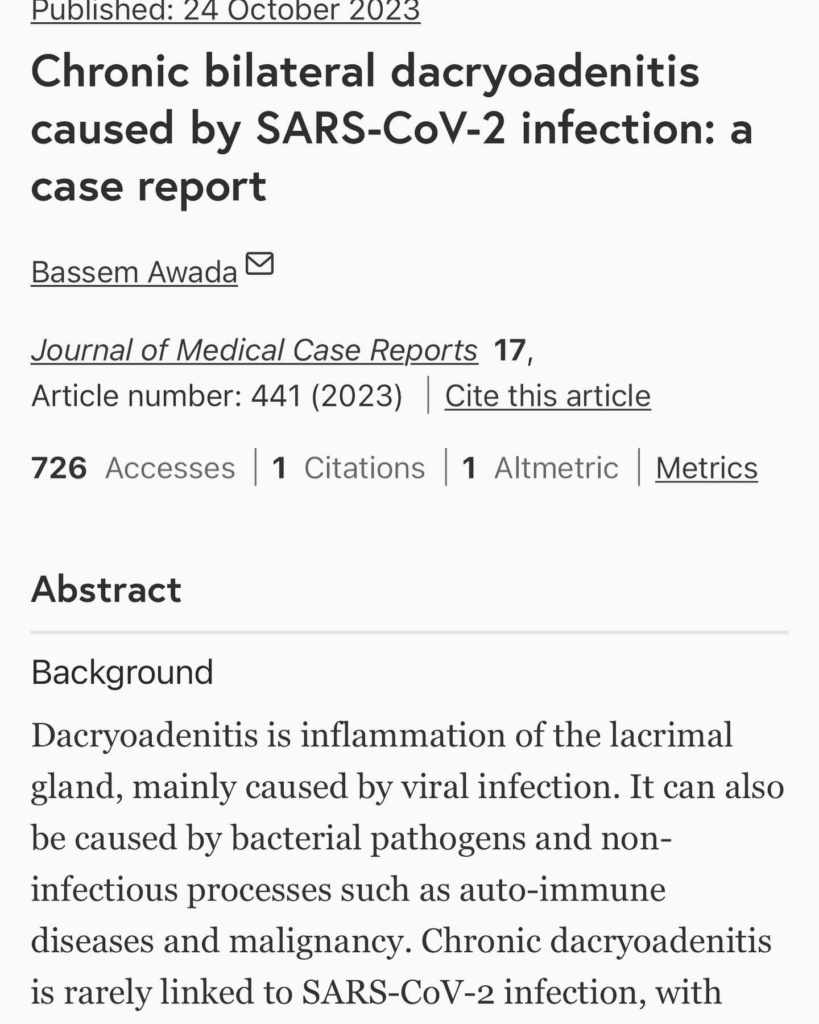

Ή μάλλον για τον τύπο που λέγεται Μάστορας. Ακούω κατά καιρούς διάφορες φήμες και έτυχε να ακούσω και τώρα κάποιες άλλες που δεν τιμούν οποίους τις διαδίδουν οπότε θα ανεβάσω μερικές φωτογραφίες από τις δύο δύσκολες τελευταίες εβδομάδες. Ο πιο σημαντικός λόγος που τις ανεβάζω είναι όμως για να μοιραστώ την ιστορία μου για την αμφοτερόπλευρη δακρυοαδενίτιδα.

Αιτία ο κοβιντ ο άτιμος… Ψάξτε το. Μπορεί και κάποιος από εσάς να υποφέρει από αυτήν αυτό τον καιρό και να μην ξέρει πώς να το διαχειριστεί.. Εγώ μπήκα στο νοσοκομείο και είχα την πιο απίστευτη γιατρό την Δήμητρα Π. να με προσέχει σε κάθε βήμα. Είμαι καλά τώρα όποτε πάμε γερά!», έγραψε χαρακτηριστικά ο Χρήστος Μάστορας.